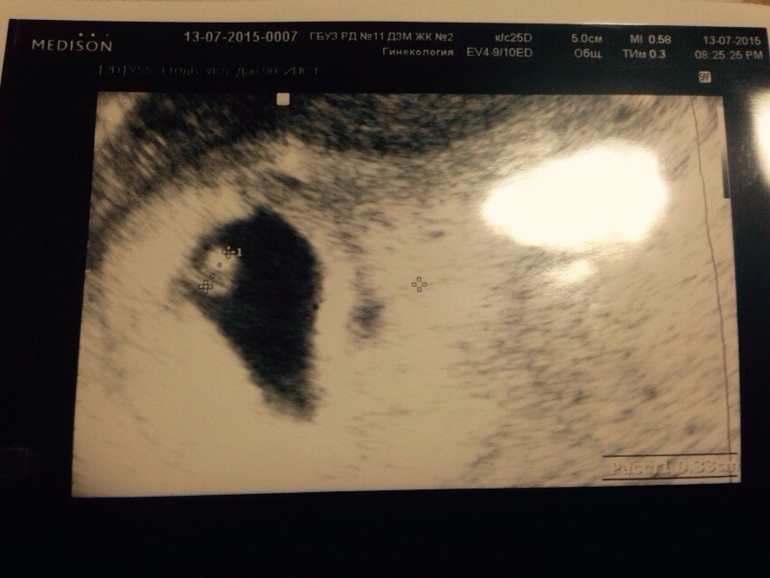

Прилагаю фото нашего первого снимка)